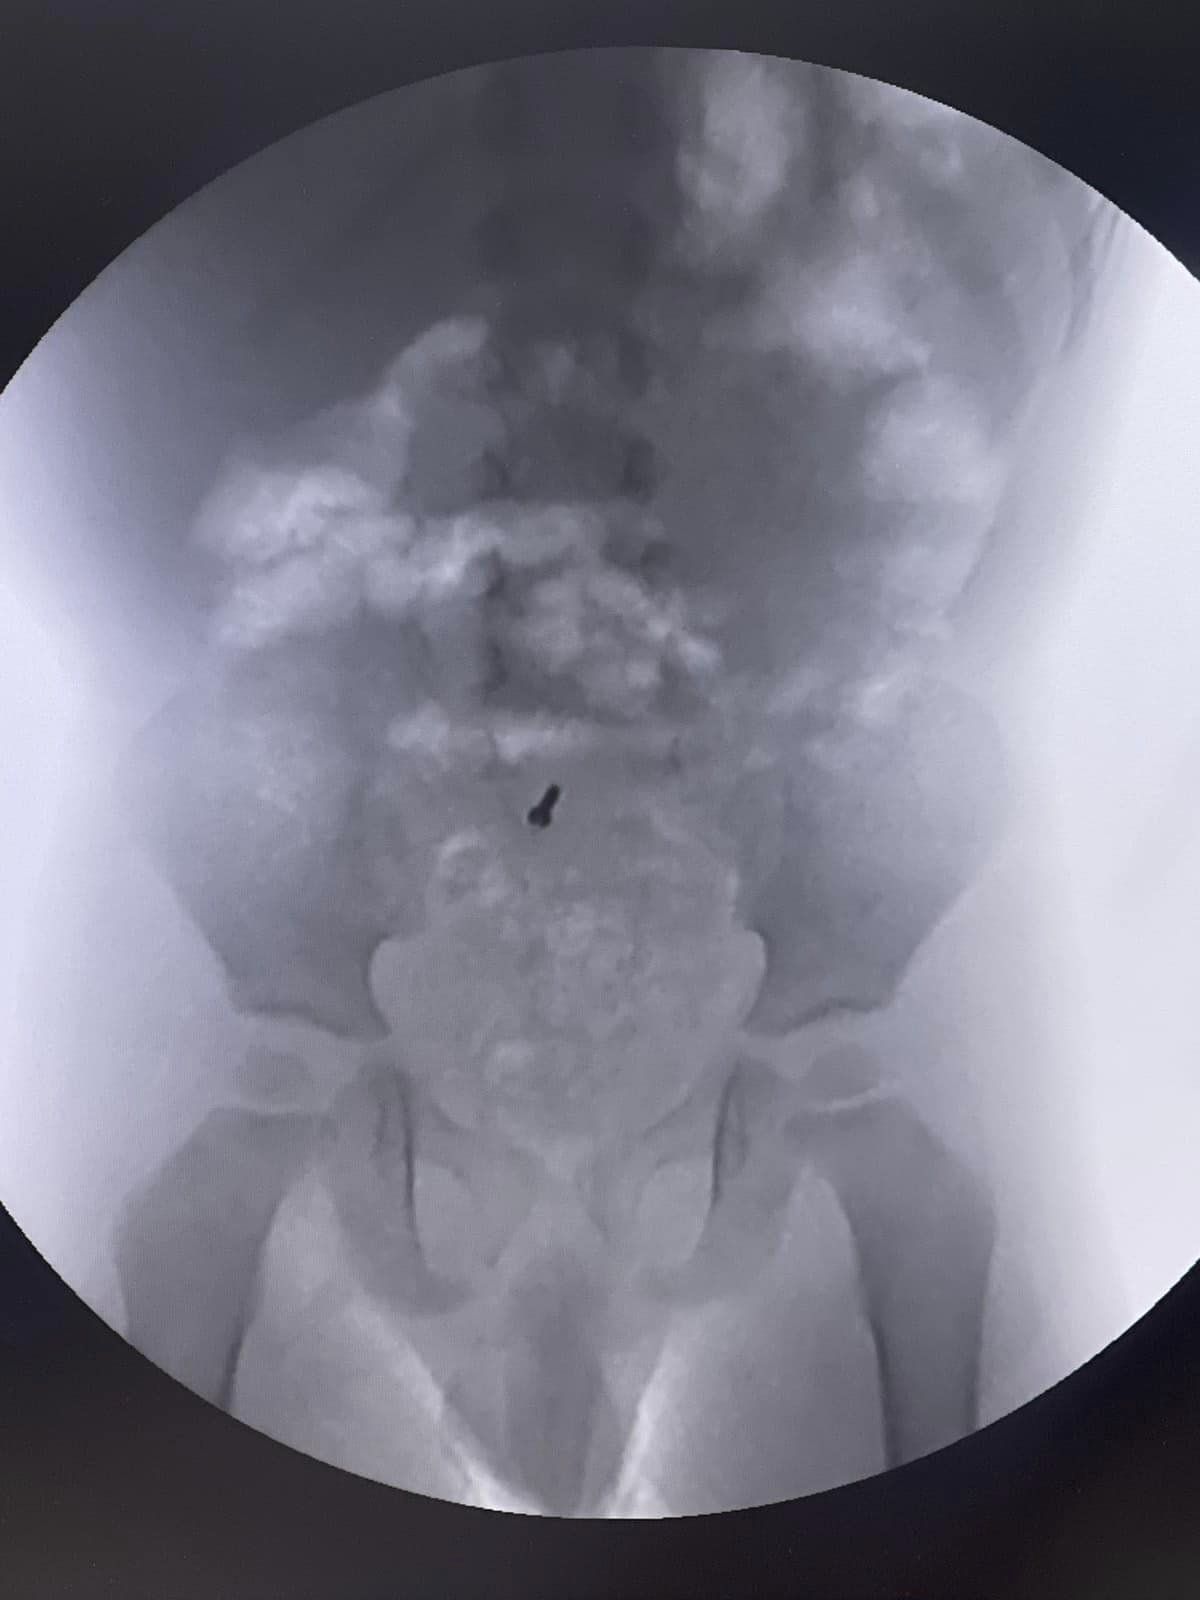

Медики разом із батьками вирішили наразі спостерігати і сподівалися, що шурупчик вийде самостійно. При повторних рентген-дослідженнях, шуруп, на жаль, залишався на місці. Про це повідомляє Львівська дитяча обласна клінічна лікарня "Охмадит", інформують "Вікна".

Батьки вирішили звернутися до Львівської обласної дитячої клінічної лікарні «Охматдит». При обстеженні дитини лікар-ендоскопіст Марта Лучак провела колоноскопію, проте шуруп не виявили.

Тоді хірурги вирішили провести діагностичну лапароскопію, перевірили весь кишківник і знайшли шуруп в апендиксі, що буває вкрай рідко. Після знахідки одразу видалили його. На третій день після операції хлопчик виписаний додому.